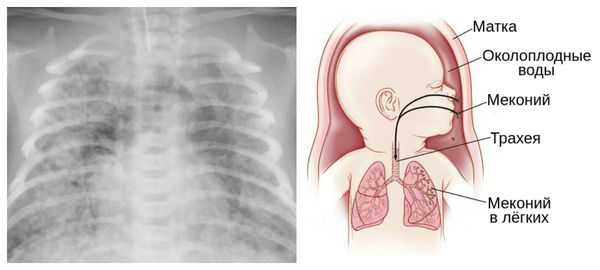

Главное — значительно увеличивается вероятность мертворождения: в 40 недель это 2-3 случая на 1000 родов, после 42-х недель — 4-7 случаев. Происходит старение плаценты, снижается количество околоплодных вод. В них может попасть меконий — первородный кал, который в норме должен отходить у младенца уже после родов. Попадая в дыхательные пути, мекониальные воды могут привести к проблемам с легкими у новорожденного.

Осложнения перенашивания беременности

Для плода большую опасность представляет асфиксия (острая гипоксия) и отслойка плаценты. Нехватка кислорода внутри утробы стимулирует плод выполнить несвоевременные дыхательных движения. Они приводят к заглатыванию вод и возможному воспалению лёгочной ткани — пневмониту. Если в водах есть примесь мекония (первородного кала), то велика вероятность мекониальной аспирации — проникновения содержимого кишечника новорождённого в его лёгкие.